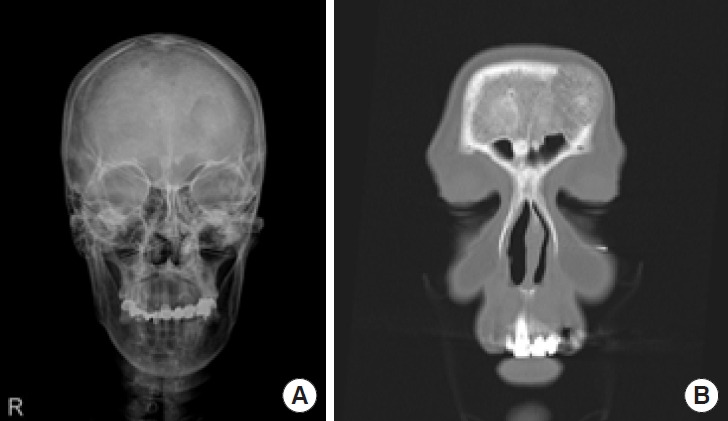

一名 59 岁的妇女因额头上有一个 3.5×3 厘米的突出肿块前来就诊。头颅 X 光片显示左侧额骨有放射状溶骨病变。此外,计算机断层扫描显示,一个 3.1× 1.7× 3.6 厘米的肿块呈 "旭日 "状,位于颅骨外板和内板之间,左侧额窦的上方和外侧。这种形态提示存在骨内血管畸形(IVM)。通过双冠状切口接近病灶。在不损伤暴露的额窦粘膜的情况下,对肿块和周围约 0.5 厘米的正常骨骼进行了整块切除。外露的粘膜用耳廓瓣进行了加固,并用骨水泥进行了颅骨成形术,以修复由此造成的骨缺损。病理检查确诊为骨内海绵状畸形,具有海绵状和毛细血管混合组织学特征。我们报告了这例 IVM 病例,并回顾了现有文献,强调了手术后令人满意的功能和美学效果。

A 59-year-old woman presented to our clinic with a 3.5× 3-cm protruding mass on her forehead. A skull X-ray revealed a radiolucent osteolytic lesion on the left side of the frontal bone. Additionally, computed tomography showed a 3.1× 1.7× 3.6-cm mass exhibiting a "sunburst" pattern situated between the outer and inner tables of the skull, just superior and lateral to the left frontal sinus. This pattern suggested the presence of an intraosseous vascular malformation (IVM). The lesion was approached via a bicoronal incision. En-bloc resection was performed, removing the mass along with approximately 0.5 cm of the surrounding normal bone without injury to the exposed frontal sinus mucosa. The exposed mucosa was reinforced with a galeal flap, and cranioplasty with bone cement was performed to repair the resulting bony defect. Pathological examination confirmed a diagnosis of intraosseous cavernous-type malformation with mixed cavernous and capillary histological features. We report this case of IVM and review the existing literature, highlighting the satisfactory functional and aesthetic outcomes after surgery.